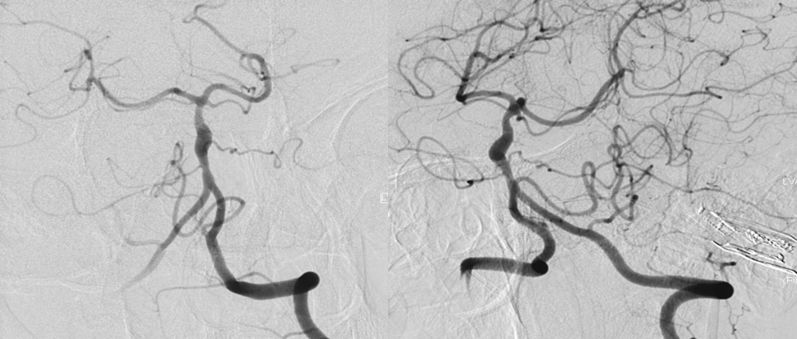

当地医院DSA:基底动脉中上段夹层动脉瘤(2019-09-10)(图3)。

图3